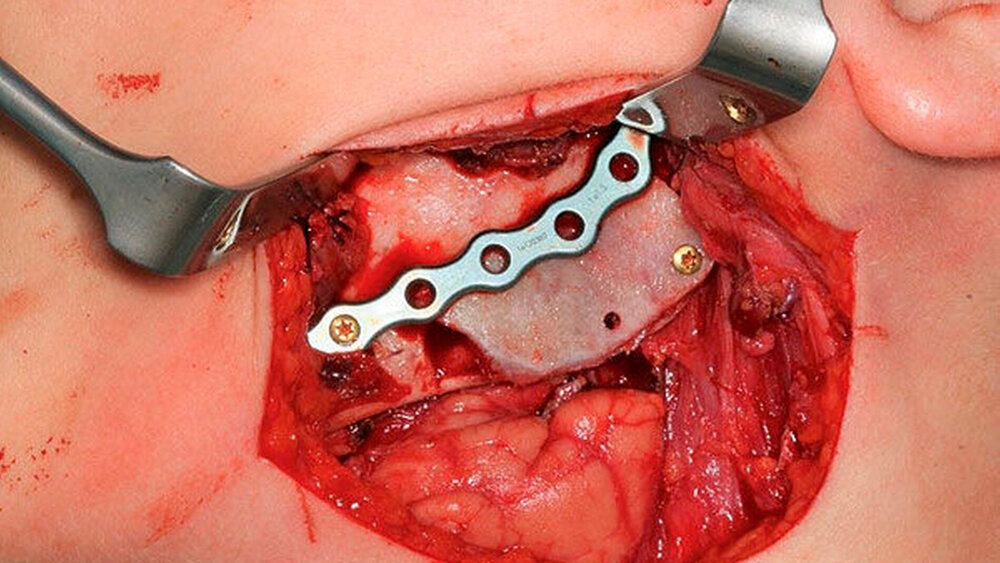

Bei bekannter histologischer Entität wurde ein einzeitiges operatives Vorgehen mit zeitgleicher Exkochleation der Raumforderung im linken Kieferwinkel sowie einer Augmentation durch ein autologes kortikospongiöses Beckenkammtransplantat festgelegt und komplikationslos durchgeführt.